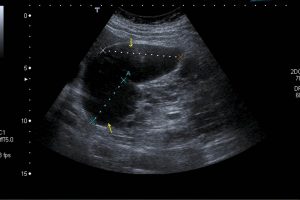

Diplomados en Ultrasonografía